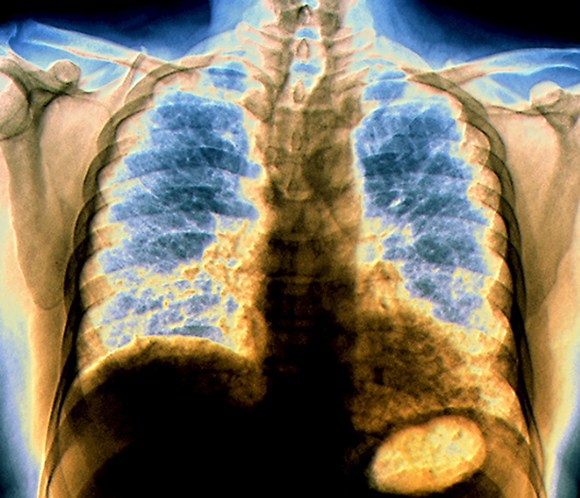

רקמת הריאות נפגעת ובמקומה נוצרת רקמת חיבור. צילום רנטגן של חולה בפיברוזיס ריאתי | Zephyr / Science Photo Library